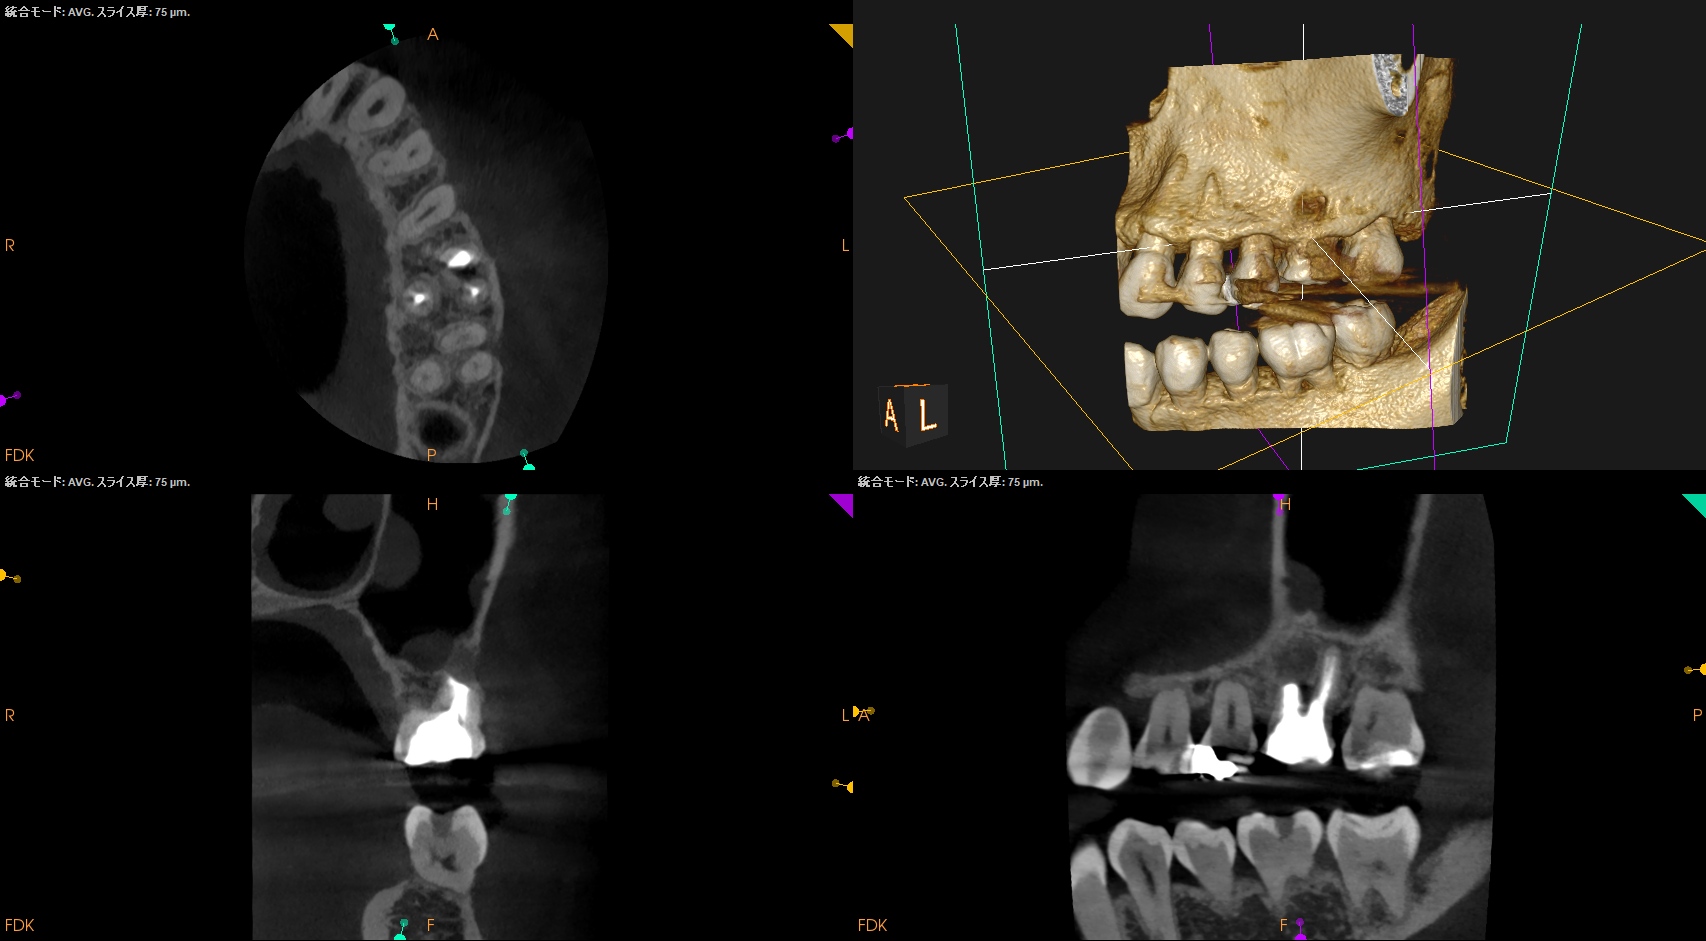

CBCT(2025.4.15)

MB

MBの根管口部あたりに穿孔が疑われる所見がある。

ストリッピングパーフォレーションというやつだ。

根充後に根管をBC Puttyで埋める必要があるだろう。

DB

P

DB,Pには何もない。

SelectiveにMBのみを扱う治療になるだろう。

さて、外科の際は

上顎洞の穿孔を避けるため、MBはCEJよりも5.6mm下方に1.3mm Osteotomyして頬舌的に4.3〜4.9mm切断する必要がある。

これはそれほど困難ではない。

その後、Root tipごと取り出す形になるだろう。